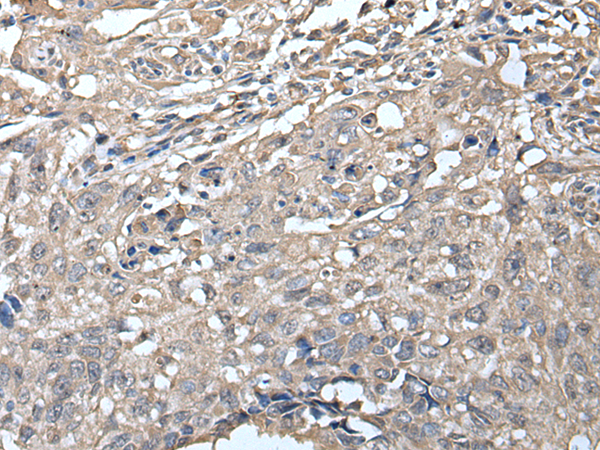

ELISA, IHC

IHC positive control:

Human thyroid cancer

IHC Recommend dilution:

20-100